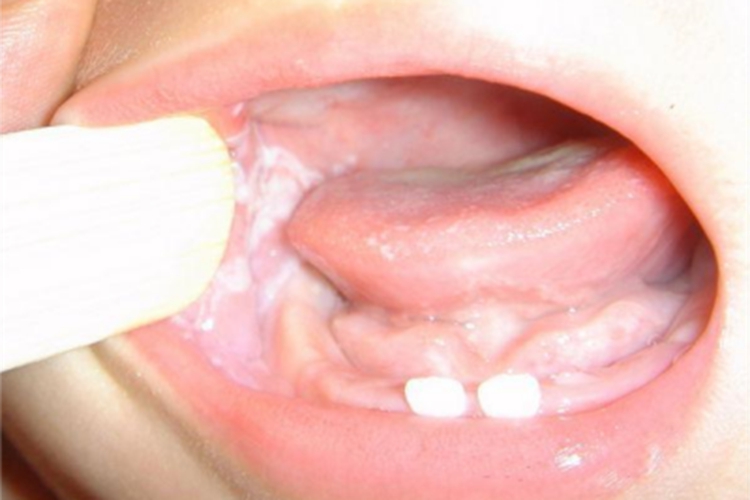

均质型口腔黏膜白斑斑块型患者的口腔黏膜上可出现白斑或白点,表面可有皲裂,平或稍高出黏膜表面,边界清楚,触之柔软,不粗糙或略粗糙,且周围黏膜多正常,患者多无症状或能感受到粗糙。